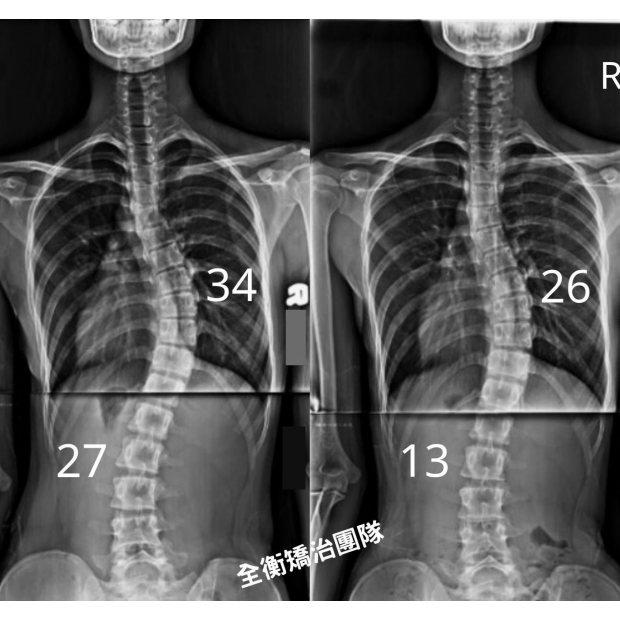

17歲脊椎側彎女孩 34度胸彎 27度腰彎

治療後追蹤,胸彎34度減少至26度,腰彎27度減少至13度 -